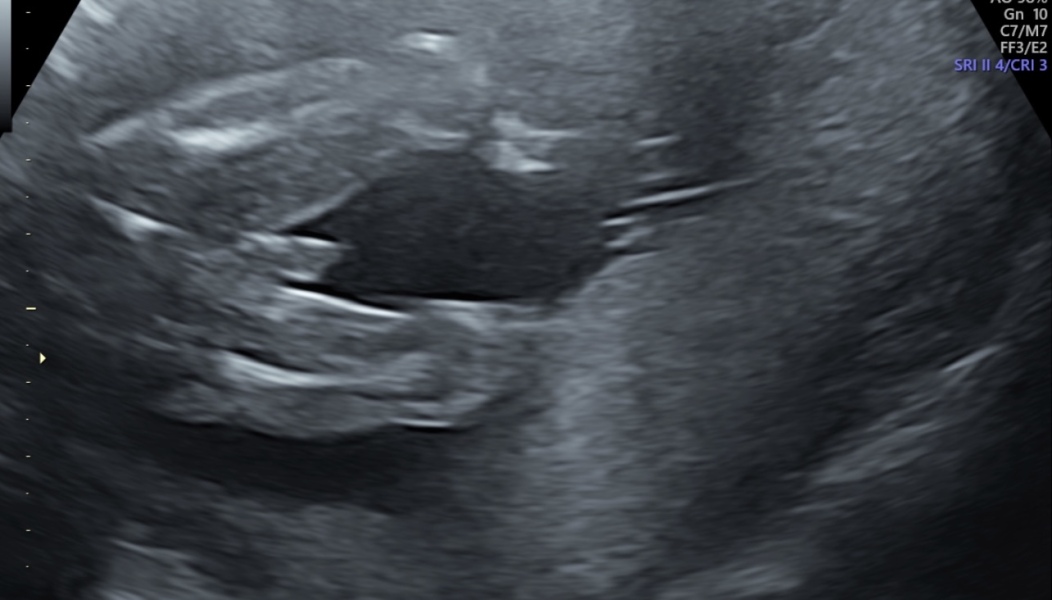

KitKatChunk96 · 18/05/2024 22:07

Hey, due 25th sep,

This is a scan at 20 weeks, theyโ€™re saying boy but Iโ€™ve been told by people it looks too thick and the line keeps going along but not as bright as the โ€œboy partsโ€ so could be cord.

hospital before this scan said itโ€™s a girl this is a re scan at a clinic that said itโ€™s a boy, but baby is laid belly down on a low lying placenta what would you all think I can update on Wednesday when hospital rescan me due to placenta

just going out my mind being told 2 different genders lol ๐Ÿ˜‚ x

@KitKatChunk96 id say thats definitely a boy! Though the angle of the scan is a bit weird. Both my boys have looked obvious like that on scan photos. I'm bias but boys are the best. My 5 year old son is very much a mummys boy and loves his cuddles.